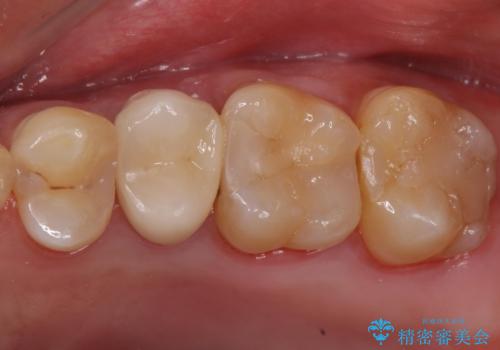

銀歯を白くして見た目を改善したい !

もげてしまった奥歯 オールセラミッククラウンでの補綴治療